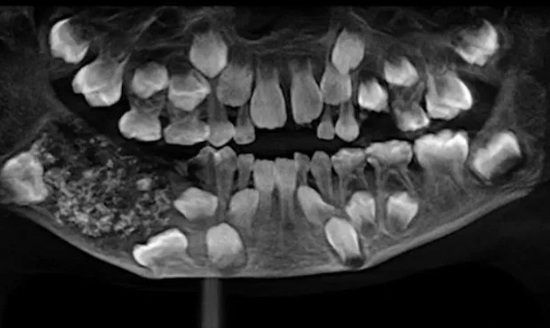

Esa hinchazón siguió creciendo hasta que finalmente el niño se sometió a una serie de estudios que indicaban la existencia de una estructura maciza de unos 200 gramos en el lado derecho de su mandíbula.

Una vez extraída en una intervención que duró hora y media, se descubrió que dentro de esa estructura había 526 piezas dentales de entre 1 y 15 milímetros.

Esta anomalía es conocida como odontoma compuesto, un tipo de tumor benigno relacionado con el desarrollo dental.

"La radiografía y la tomografía mostraron múltiples dientes rudimentarios en un tejido similar a una bolsa", sostuvo el doctor Senthilnathan, profesor del Departamento de Cirugía Oral y Maxilofacial de Saveetha, según citó el diario El Comercio de Perú.